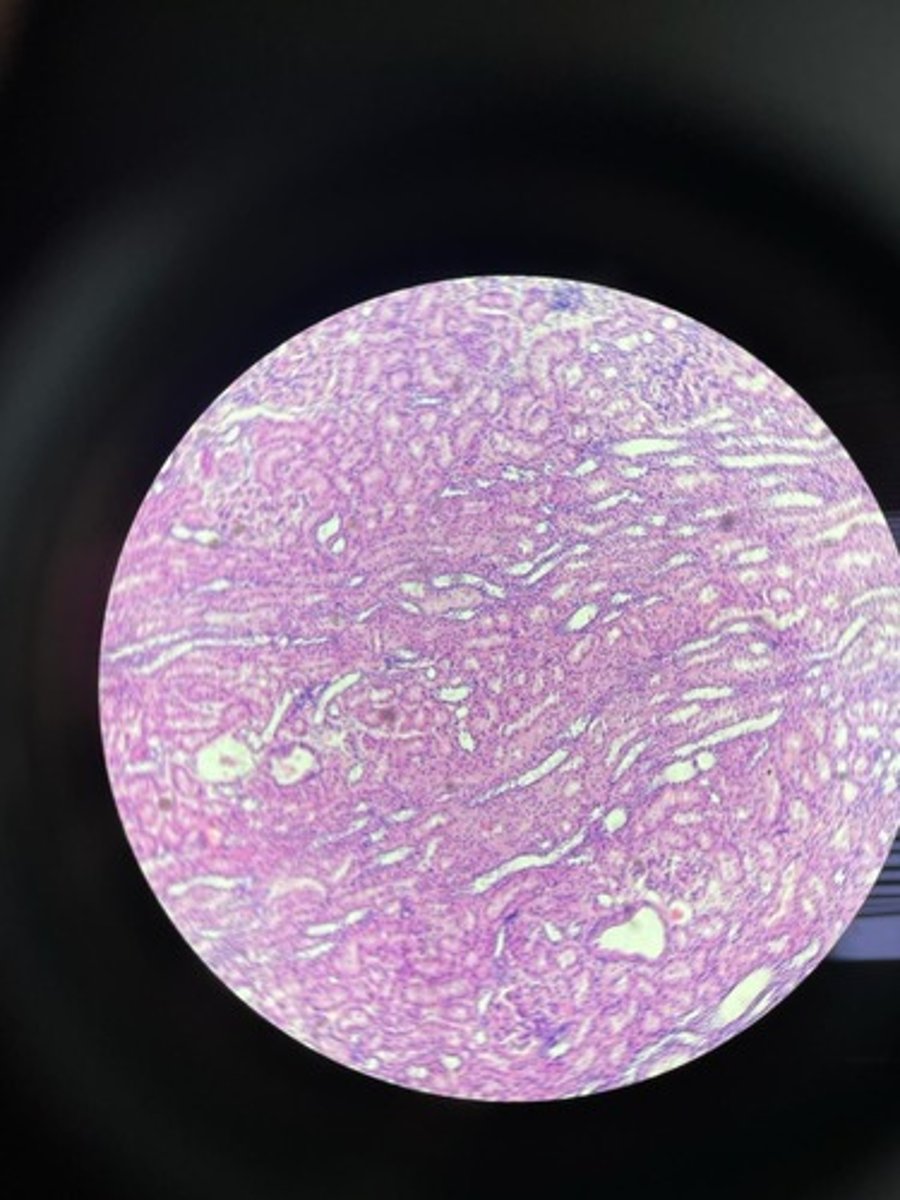

Kidney HE

Kidney HE

Kidney HE

Kidney HE

Kidney HE